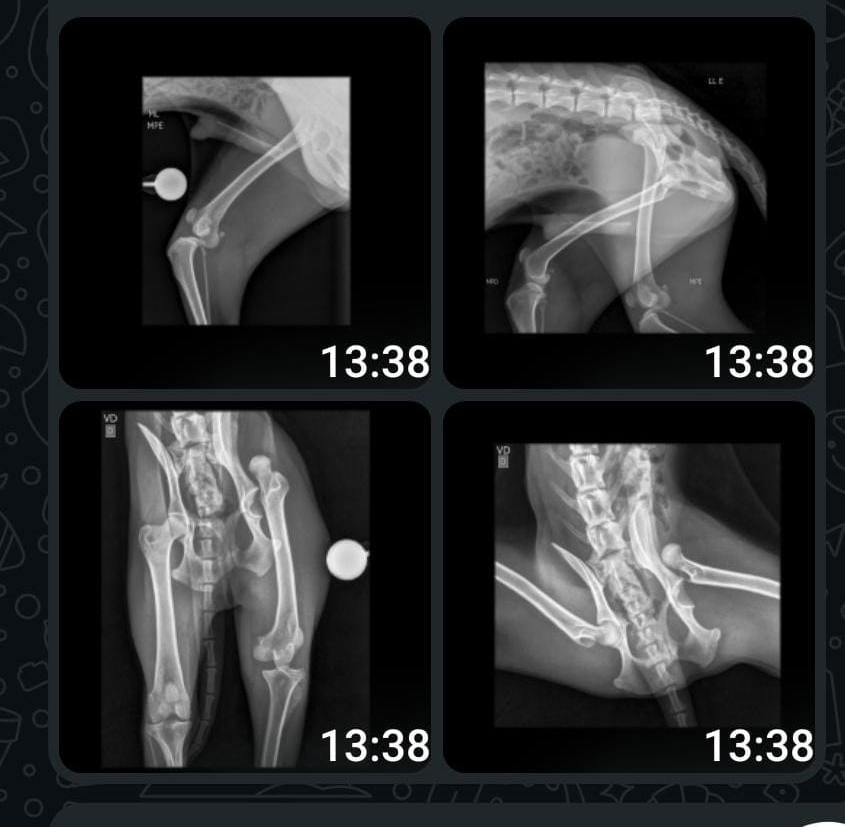

De acordo com a entidade, há indícios de que o animal tenha sido atropelado. Ele foi encaminhado para atendimento veterinário e passou por exame de raio-x logo nas primeiras horas da manhã. A ONG alertou que o quadro inspira cuidados.

“Já levamos o cachorro para realizar o exame de raio-x cedo. Infelizmente, acreditamos que o resultado não será bom”, informou a Associação de Proteção Animal.